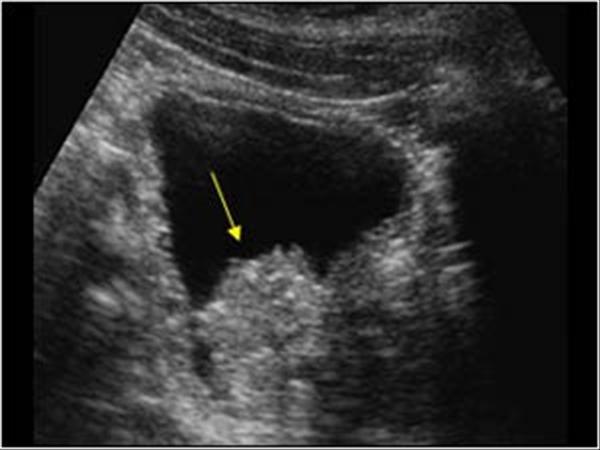

Mirizzi SYndrome

impacted stone in the cystic duct or GB neck

presence of two tubular structures representing the bile duct above the level of the cystic duct

Mirizzi SYndrome

impacted stone in the cystic duct or GB neck

presence of two tubular structures representing the bile duct above the level of the cystic duct